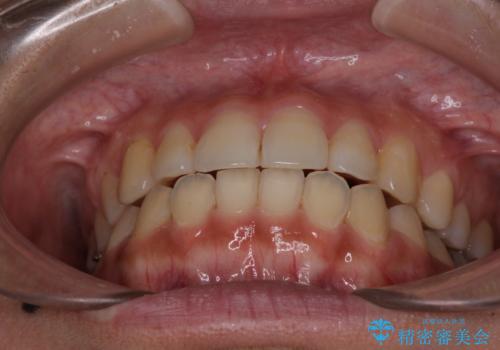

前歯の突出感とデコボコ インビザラインで改善

- 上下前歯のデコボコを気にして来院された患者様です。

インビザラインによる上下歯列の側方拡大と後方移動、IPR(歯と歯の間を削る)にるスペースの獲得により歯列を整えることとしました。

右上の小臼歯は歯根癒着をしており、様々な方法を試みるも動かすことができませんでした。

それでも奥歯のかみ合わせに不自由はなく、歯列をきれいに整えることができました。